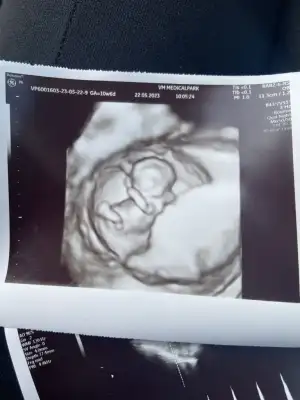

Bebek şükür iyi.

9+4 olmuş.

Rahim ağzı uzunluğuna baktı normal iyi dedi.

3.5 santim dedi.